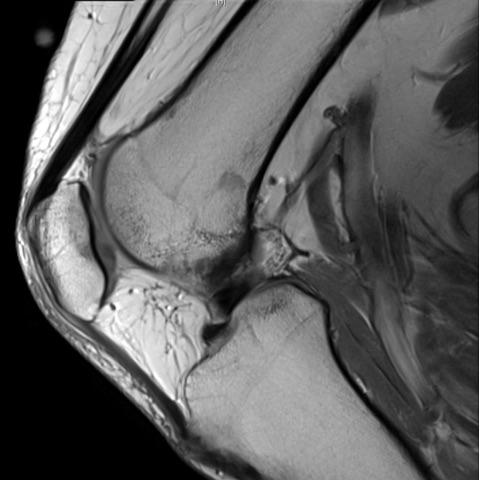

| The Case Of The Unextendable Knee - Page #3 | |||